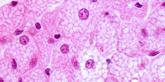

As adipose tissue expands, it becomes a hotbed of immune activity, attracting macrophages, key immune cells that adapt to their surrounding environment. In lean individuals, most macrophages in adipose tissue exhibit an anti-inflammatory M2 phenotype, functioning like maintenance workers that support tissue repair and balance. However, in obesity, macrophages shift toward a pro-inflammatory M1 phenotype, acting more like alarm responders. These activated M1 macrophages release additional cytokines, including tumor necrosis factor-alpha (TNF-α) and monocyte chemoattractant protein-1 (MCP-1), which recruits even more immune cells. This infiltration sets off a feed-forward loop of inflammation, progressively worsening local tissue dysfunction and contributing to systemic metabolic disturbances. [2]

The inflammatory environment within expanding adipose tissue also creates cellular stress, placing significant strain on mitochondrial function. Elevated levels of reactive oxygen species (ROS)—highly reactive byproducts of chronic inflammation—act like corrosive exhaust, damaging mitochondrial DNA and proteins. This damage impairs the mitochondria's ability to efficiently generate energy through oxidative phosphorylation, much like an engine losing power due to wear and tear. With reduced mitochondrial efficiency, the capacity for fatty acid oxidation declines, causing excess lipids to accumulate further in tissues. [2]

This cycle of inflammation, mitochondrial dysfunction, and reduced energy expenditure forms a self-reinforcing loop—akin to a system stuck in a downward spiral—that accelerates the progression of obesity and metabolic disease.